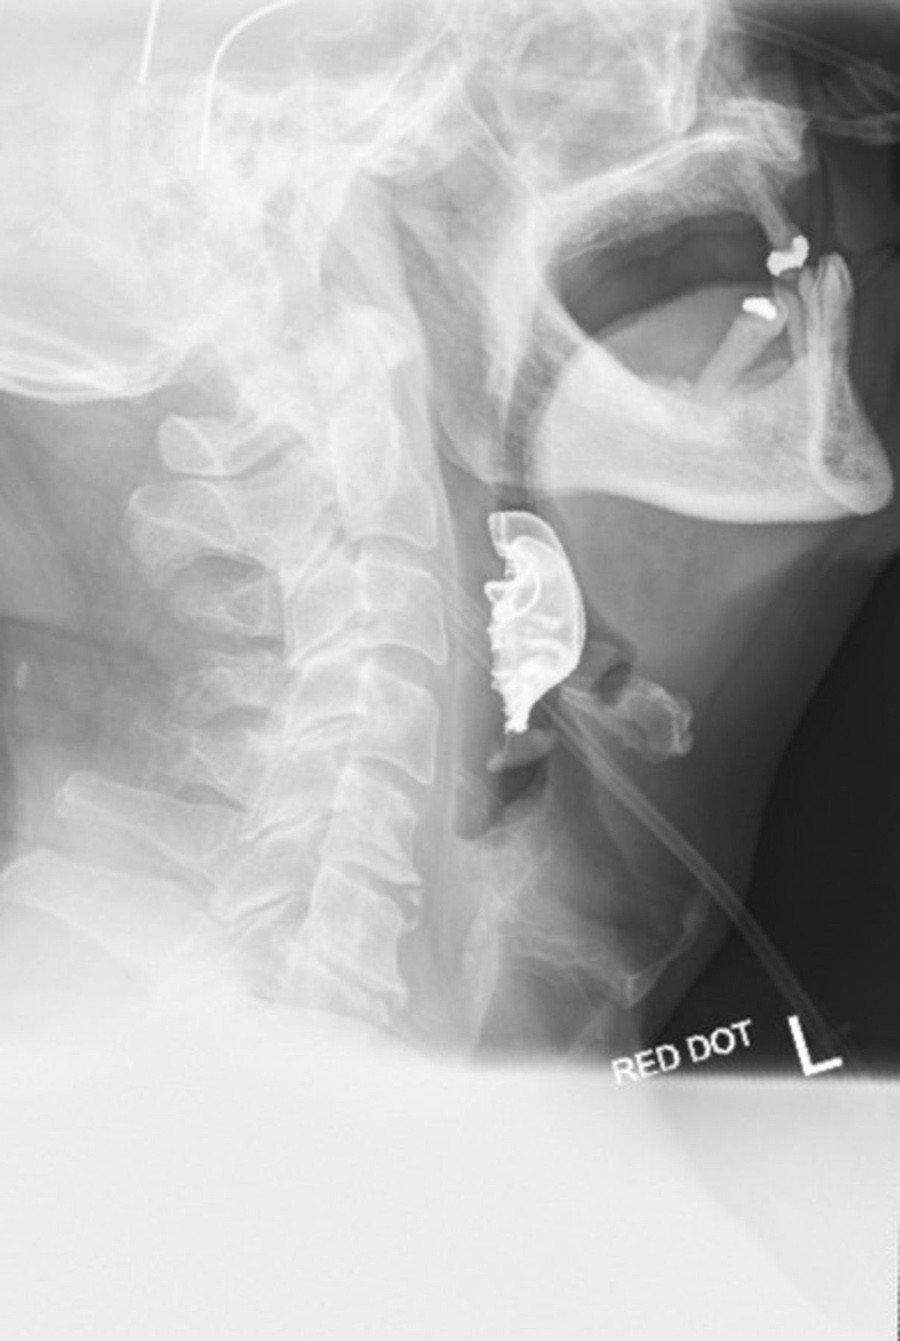

Dos días después regresó al centro de salud porque sus síntomas se habían agudizado: no había podido siquiera ingerir los medicamentos, tenía dificultad para respirar, principalmente al estar acostado, y el sangrado continuaba. Entonces los especialistas le revisaron la garganta y detectaron un objeto extraño sobre sus cuerdas vocales. Luego de una radiografía de cuello se pudo comprobar que se trataba de una pieza compuesta de tres dientes y un puente metálico.